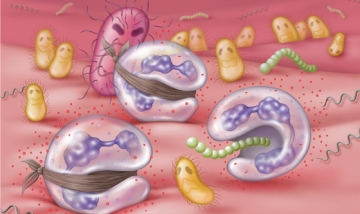

A fő oka a ínybetegségek patogén baktériumok élő a szájüregben bármilyen személy fenntartása a természetes mikroflóra.

Ez kezdődik a folyamat ellenőrizetlen szaporodását mikrobák okozó gyulladás, fájdalom, viszketés és kellemetlen érzést a kapcsolódó feltételek folyamatosan.